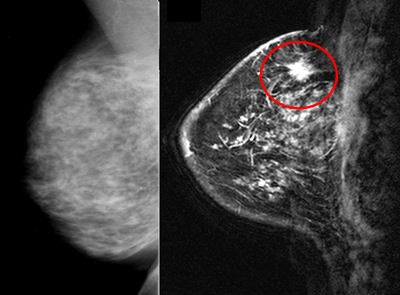

| A 76-year-old woman with 1.4-cm contralateral lesion noted on MR (right) after a negative mammogram (left). Image courtesy of Dr. Johnny Ray Bernard Jr. |

Mayo Clinic in Jacksonville traditionally has used MRI as an adjunct to mammography. "Particularly in women with dense breasts, mammograms have a difficult time trying to discern between breast tissue and what is abnormal," Bernard said. "With MRI, the picture comes out more clearly, so it is usually easier for MRI to distinguish between dense tissue and abnormalities."